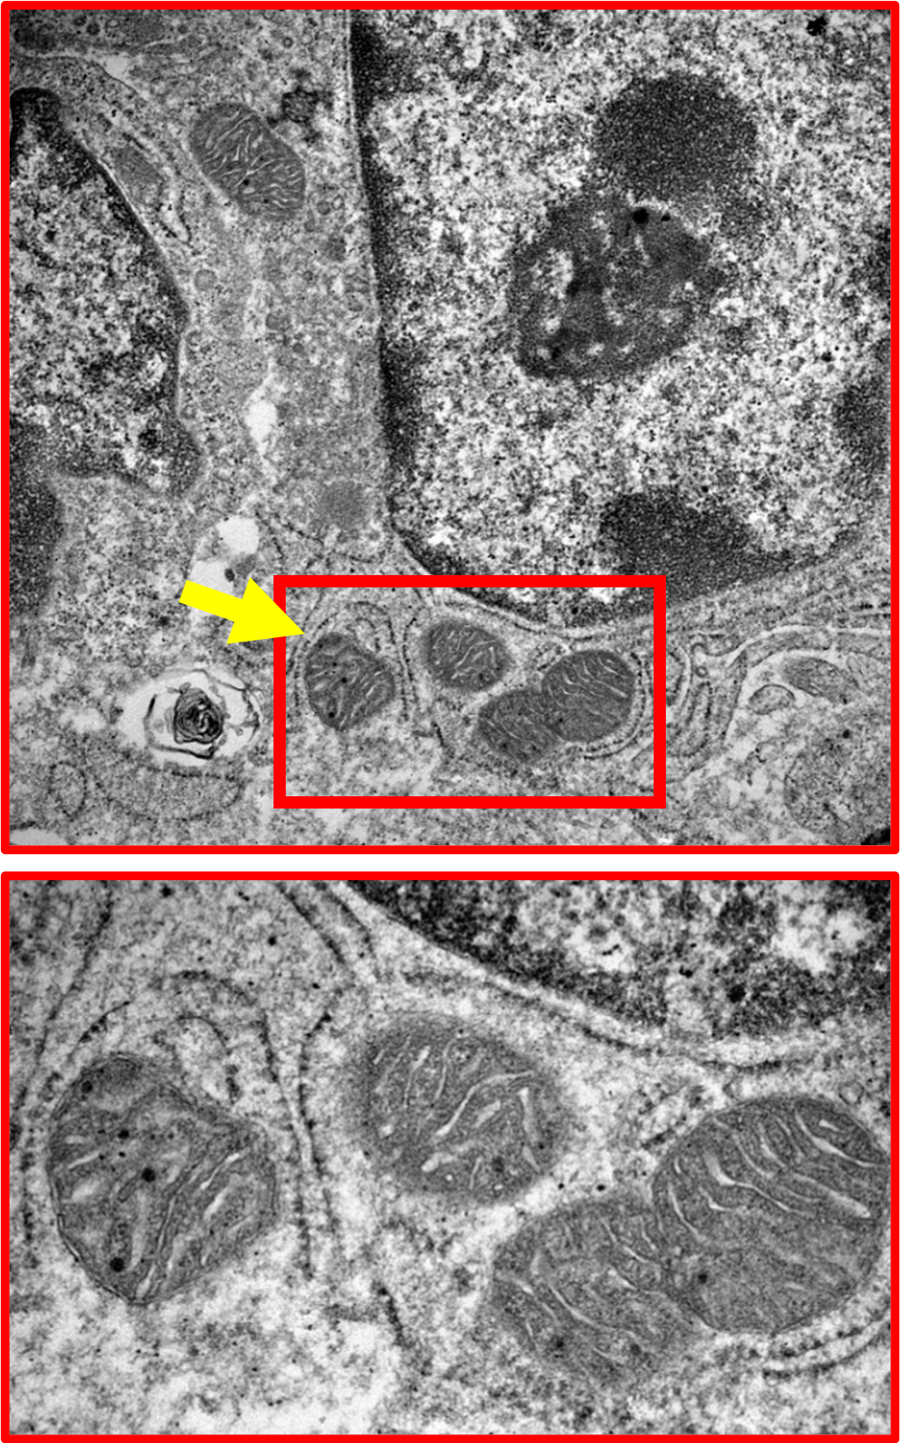

Figure 1: Mitochondria (‘Batteries’ or ‘Powerstations’) in the gut lining cells (yellow arrows). All cells have mitochondria, which are descended from ancient bacteria 3 billion years ago. Mitochondria produce energy for cells but are also important for many other functions including in controlling immune and inflammation responses. Electron micrograph with magnification of >100 times.

The bottom panel is a zoomed-in version of the top panel.

In 2010, I made the observation that there were high levels of mitochondrial damage (damage to the ‘batteries’ of the cell, see figure 1) in the gut lining of mouse IBD models (mice that scientists use in the lab to better understand the biology of IBD.) More recently, we have also observed this in humans. Not much was known about this then, but it has now been shown that damaged mitochondria can cause inflammation. Following work funded by MRC and Crohn’s & Colitis UK, we came up with the idea that treating the damaged mitochondria might be beneficial for Ulcerative Colitis (UC).